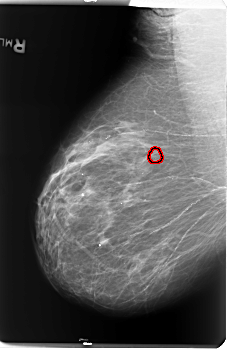

B_3141_1.RIGHT_MLO

RIGHT_CC LINES 5880 PIXELS_PER_LINE 3472 BITS_PER_PIXEL 12 RESOLUTION 50 OVERLAY

FILE: B_3141_1.RIGHT_CC.OVERLAY

TOTAL_ABNORMALITIES 1

ABNORMALITY 1

LESION_TYPE CALCIFICATION TYPE PLEOMORPHIC DISTRIBUTION CLUSTERED

ASSESSMENT 4

SUBTLETY 3

PATHOLOGY BENIGN

TOTAL_OUTLINES 1

BOUNDARY